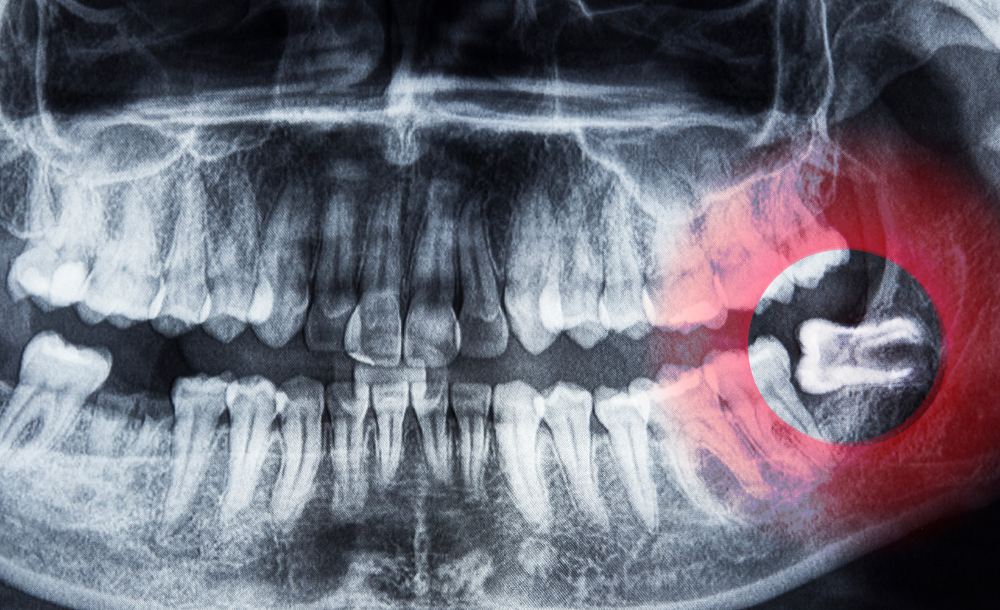

Wisdom teeth, or third molars, usually erupt between the ages of 17 and 25. In many cases, they can cause pain, crowding, infection, or damage to nearby teeth if there isn’t enough space for them to grow properly. At The Family Dental Clinics, we offer safe and comfortable wisdom teeth removal to protect your oral health and relieve discomfort.

Consultation & X-rays – To assess position and condition of the teeth